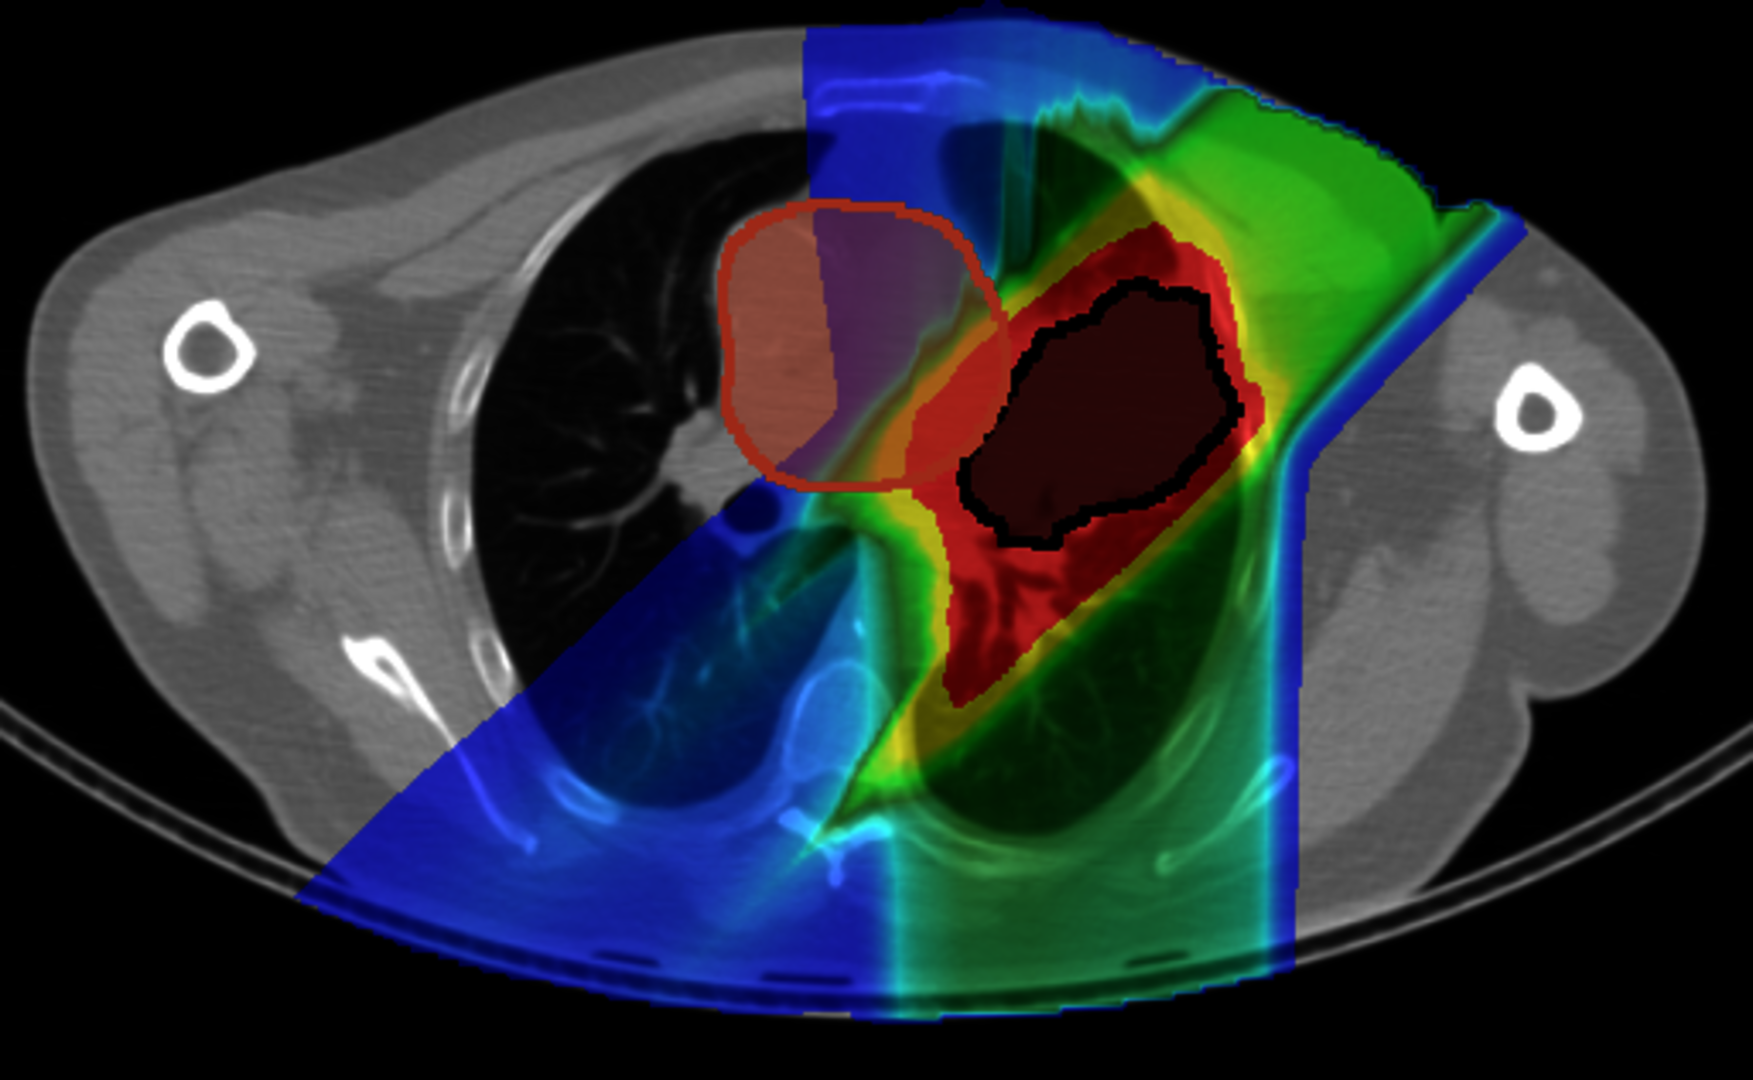

In addition, at GSI, we are leading the investigation of upright carbon ion therapy for lung cancer patients. In a collaboration with Northwestern Medicine Chicago Proton Center, we have conducted an extensive comparison of treatment plans between postures.